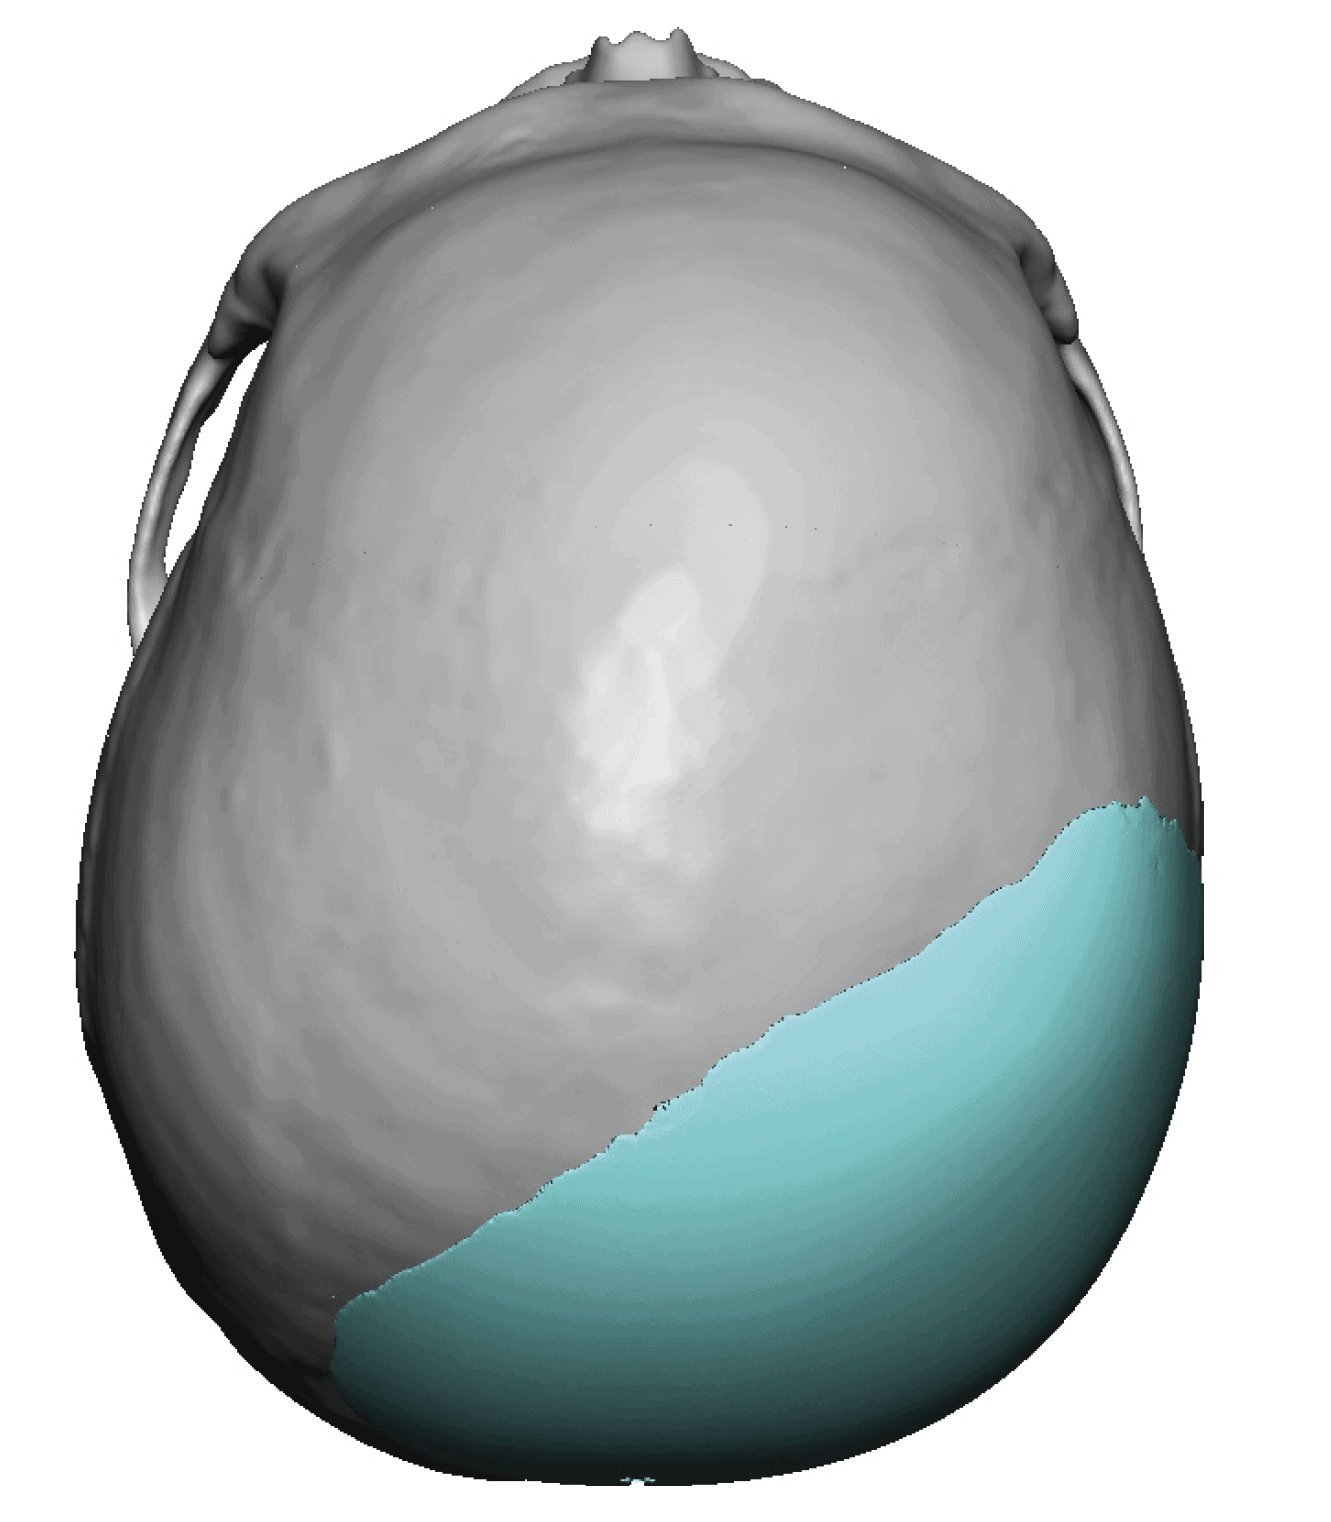

Patient 28

Desire for rounder shape to the top of the head from a congenital parasagittal deficiency skull shape.

Custom skull implant designed to fill in the parasagittal deficiencies.

Desire for rounder shape to the top of the head from a congenital parasagittal deficiency skull shape.

Custom skull implant designed to fill in the parasagittal deficiencies.